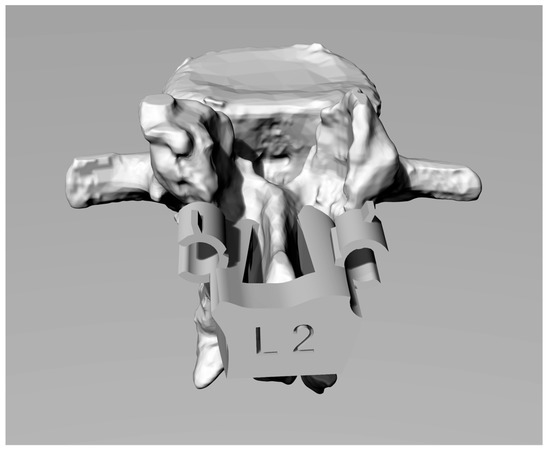

Segmentation generates 3D Standard-Triangulation-Language (STL) models of the vertebrae that were imported into Geomagic software (3D Systems— Rock Hill (SC), USA) for conversions in poli-surfaces format (IGES). This step is particularly useful because the IGES model is composed by closed surfaces that are suitable for processing with CAD modelling software. After the conversion into IGES format, the vertebral model was imported using the Rhinoceros Software (Robert McNeel & Associates—Seattle, WA, USA). Figure 1 shows a 3D reconstruction.

Figure 1. Computer-aided-design (CAD) reconstruction of a lumbar vertebra.